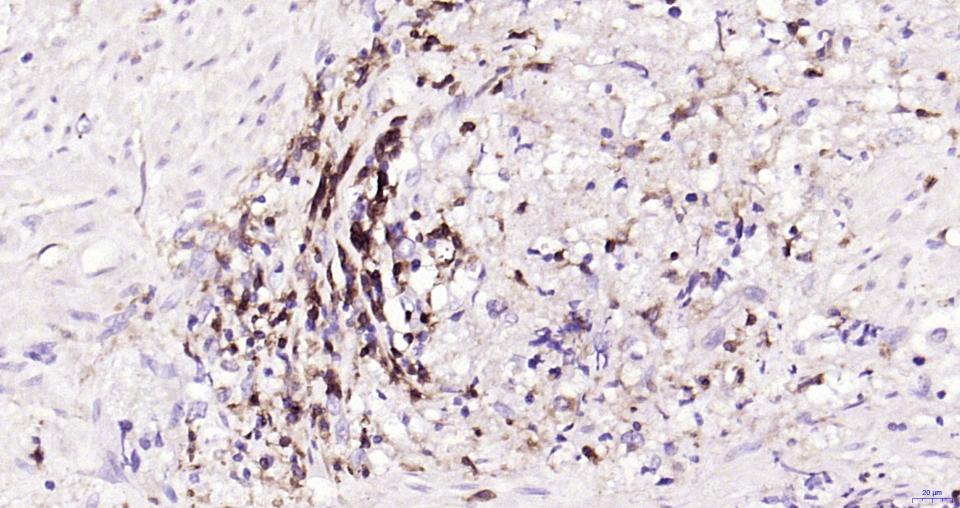

| IHC-P | Human | 1:100-500 | |